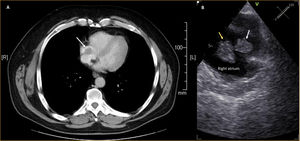

We present the case of a 60-year-old asymptomatic male patient with a medical history of rectal adenocarcinoma under chemotherapy, with a totally implantable venous access port (TIVAP). A staging computed tomography scan showed an intracardiac mass (Figure 1, Panel A) and the transesophageal echocardiography confirmed the presence of two extremely mobile masses in the right atrium, adherent to the tip of the TIVAP, the larger of the two measuring 20 mm × 20 mm (Figure 1, Panel B). Due to the patient's high risk of bleeding, anticoagulation with enoxaparin was started and, after one week, the thrombus was re-evaluated; it maintained the same dimensions and mobile appearance. After discussion in the heart team, we decided to perform a mechanical thrombectomy, with extracorporeal membrane oxygenation prepared, if needed.